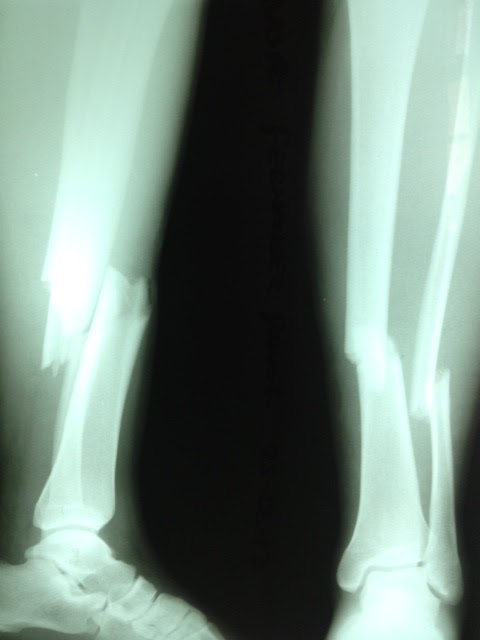

The initial phase of the program was the introduction of the equipment and instruction in the appropriate technique. Alongside Dr. Cesar Aranguri, Director of the Mission, I led an instructional course for the orthopedic surgeons in Ayacucho. Over the following week, I assisted two Ayacucho surgeons, Dr. Prado and Dr. Romero, on two cases. The first was a 10 year old girl who had had a femur fracture 6 months earlier that had failed to heal despite previous surgery. The second was an open tibia fracture in a young man who fell off a horse. Both cases were quite successful.